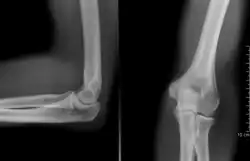

Projectional radiography of the knee in a modern X-ray machine | |

Projectional radiography

The creation of images by exposing an object to X-rays or other high-energy forms of electromagnetic radiation and capturing the resulting remnant beam (or "shadow") as a latent image is known as "projection radiography". The "shadow" may be converted to light using a fluorescent screen, which is then captured on photographic film, it may be captured by a phosphor screen to be "read" later by a laser (CR), or it may directly activate a matrix of solid-state detectors (DR—similar to a very large version of a CCD in a digital camera). Bone and some organs (such as lungs) especially lend themselves to projection radiography. It is a relatively low-cost investigation with a high diagnostic yield. The difference between soft and hard body parts stems mostly from the fact that carbon has a very low X-ray cross section compared to calcium.